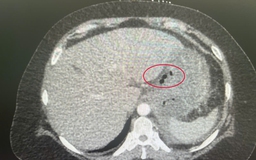

Sốt cao liên tục 8 ngày, nhập viện phát hiện hai ổ áp xe lớn trong gan